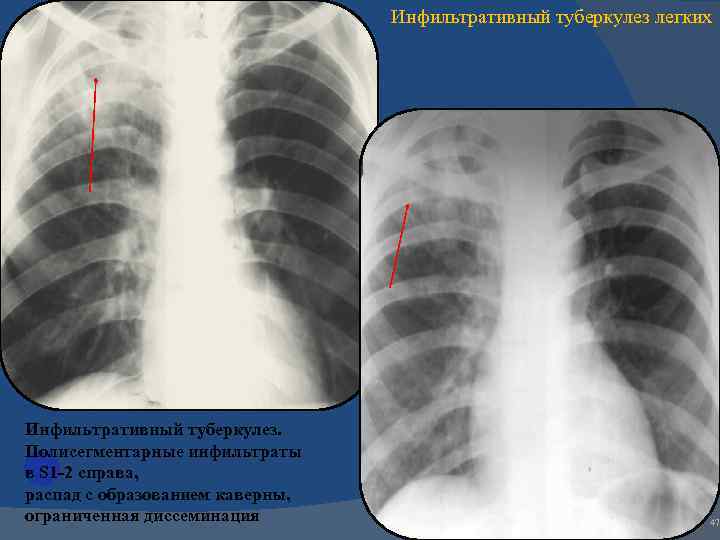

Симптомы и лечение инфильтративного туберкулеза легких

Раздел: Снимки-откровения